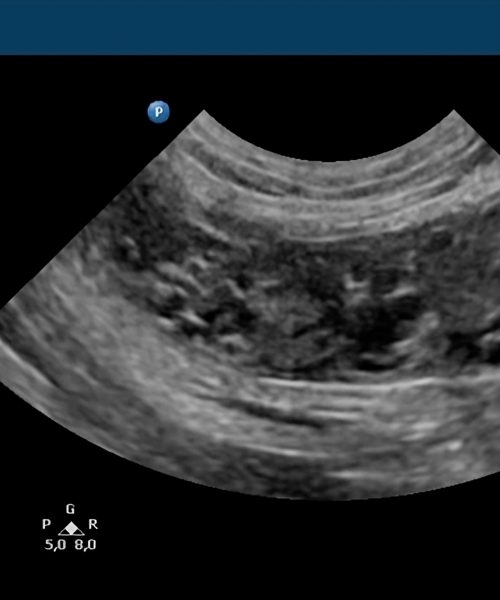

Valido la precisión diagnóstica comparando las imágenes ecográficas con los hallazgos quirúrgicos reales.

Garantizo transparencia y confianza exhibiendo en este apartado casos reales con su correlación intraoperatoria documentada.